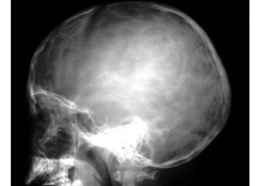

醫(yī)學(xué)影像學(xué)骨骼系統(tǒng)復(fù)習(xí)重點(diǎn)【全】

醫(yī)學(xué)影像學(xué)骨骼系統(tǒng)復(fù)習(xí)重點(diǎn)